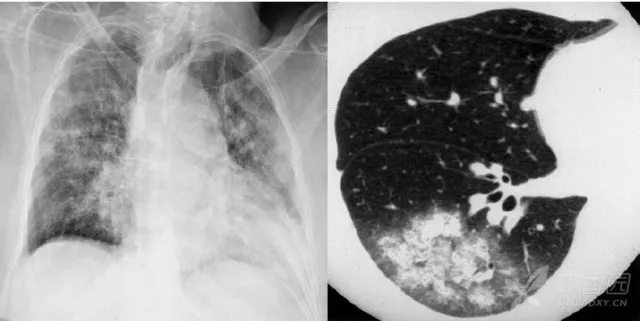

大葉性肺炎胸部影像

簡單來講,肺炎出現(xiàn)較大的病灶,局限在一個肺葉,就叫大葉性肺炎。大葉性肺炎也叫肺泡性肺炎,這是因?yàn)榇笕~性肺炎的炎性滲出主要發(fā)生在肺泡。細(xì)菌、病毒、真菌、以及肺炎支原體等非典型病原體都可以引起大葉性肺炎。